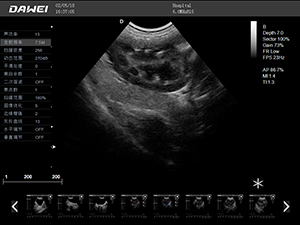

F5-VET彩色多普勒動物超聲診斷儀

F5-VET是一款性能可靠的獸用全數字彩色多普勒超聲診斷系統,基于Windows平臺 配置固態盤快速啟動 穩定可靠,融合了全面豐富的臨床應用,結合優異的人機工程學設計,推動了臨床診斷新趨勢。

·中小動物的肝、膽,脾、腎、膀胱、子宮、妊娠等各組織器官的檢查和病變的診斷